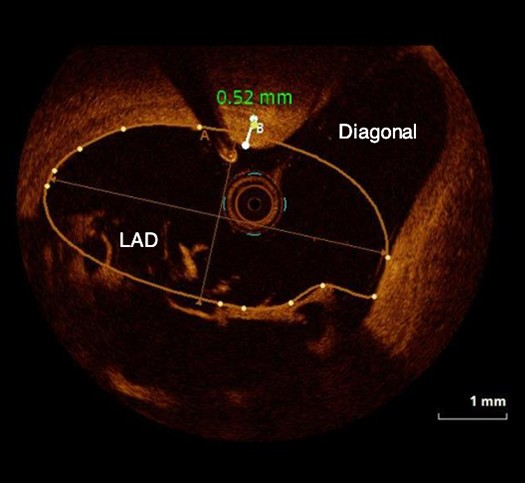

Catéter para toma de imágenes coronarias Opticross de 40 MHz vs. Catéter para toma de imágenes coronarias Opticross de 60 MHz

El Catéter para toma de imágenes coronarias Opticross de 60 MHz proporciona una mayor visibilidad del stent con una resolución más clara para confirmar la aposición adecuada del stent a la pared del vaso.

OPTICROSS 60 MHz

Catéter de imágenes OPTICROSS HD 60MHz

Resolución axial: 22 µm